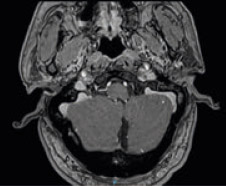

Paciente de 63 años de edad, sin anteceden-tes personales de interés, que acude a con-sulta de Otorrinolaringología por hipoacusia bilateral, más acusada en el oído derecho. El paciente fue diagnosticado de enfermedad de Ménière de oído derecho en otro centro hace más de 15 años. Debutó con crisis ver-tiginosas y acúfeno derecho, las crisis fueron desapareciendo progresivamente a la vez que fue aumentando la hipoacusia derecha. En la explora-ción la otoscopia es normal y la exploración neurovestibular no muestra hallazgos patológicos. Se le realiza una audio-metría en la que se observa una hipoacusia neurosensorial bilateral de 80 db en el oído derecho y de 70 db en izquier-do. Según refiere el paciente se le propuso una prueba de imagen cuando comenzó con la clínica pero negó por claustrofobia, por lo que se le propone la realización de RMN craneal, de oído interno y ángulos pontocerebelosos con contraste y el paciente acepta. La cual informa que en ambos ángulos pontocerebelosos se evidencia la presencia de engrosamiento nodular de los paquetes acusticofaciales compatible con neurinoma del acústico bilateral. Las dos lesiones muestran componente intracanalicular cilíndri-ca con crecimiento hacia las cisternas de los ángulos pontocerebelosos con morfología en “cono de helado”. El neurinoma izquierdo muestra un espesor de 4 mm en su porción intracanalicular y diámetro de hasta 10 mm en el ángulo pontocerebeloso. El neurinoma derecho muestra un diámetro de 3 mm en su porción intracanalicular y diámetro de 8 mm en el ángulo pontocerebeloso. A nivel de las estructuras del oído interno no se visualiza el vestíbulo derecho aparentemente ocupado por material de partes blandas que muestra discreto realce en estudio con con-traste que podría corresponder con componente vestibular de neurinoma derecho. Buena visualización de los canales semicirculares. Estructuras de oído interno izquierdo sin alteraciones. Por lo que se concluye la existencia de una tumoración bilateral del ángulo pontocerebeloso compati-ble con neurinoma del acústico bilateral que muestra un componente intracanalicular que se extiende a los ángulos pontocerebelosos. En el oído derecho se asocia ocupación del vestíbulo que podría corresponder con componente vestibular del neurinoma.